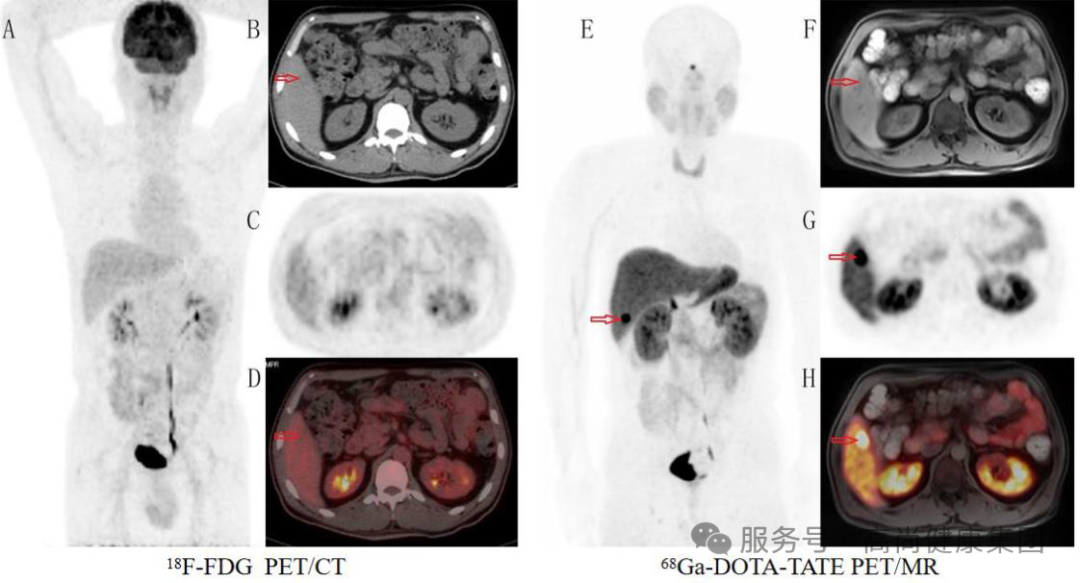

18F-FDG PET/CT(图 A-D)示肝右叶下段等-稍低密度结节影,代谢与周围肝脏组织相仿;

68 Ga-DOTA-TATE PET/MR(图 E-H)示肝右叶下段结节 PET 阳性,考虑神经内分泌瘤转移,可见生长抑素受体 PET 显像在该患者的复发监测中发挥了重要作用。[2]